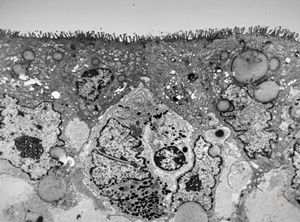

jejunum … lipid malabsorption